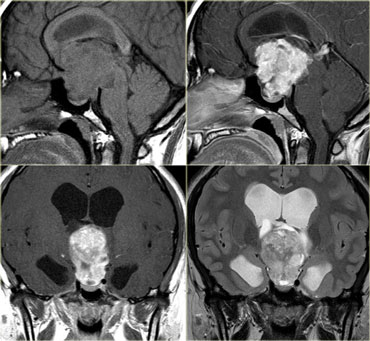

4th ventricle

In children tumors in the 4th ventricle are very common.

Astrocytomas are the most common followed by medulloblastomas (or PNET-MB), ependymomas and brainstem gliomas with a dorsal exophytic component.

In adults tumors in the 4th ventricle are uncommon.

Metastases are most frequently seen, followed by hemangioblastomas, choroid plexus papillomas and dermoid and epidermoid cysts.